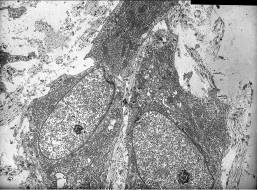

При сетке из никелида титана остов соединительной ткани, новообразованной вокруг имплантата, имеет волоконно-фибриллярный тип строения (рис. 5).

а б

в г

Рис. 5. Стереоструктурный микрорельеф поверхности имплантата из никелида титана и формирование соединительной ткани на 14 сутки после имплантации. Сканирующая электронная микроскопия. Трансмиссионная электронная микроскопия.

а – шероховатая поверхность имплантата, ув. 1300;

б - плотная фиксация элементов соединительной ткани к поверхности имплантата и их циркулярная ориентация, СЭГ, ув. 1100;

в – активные фибробласты и направленная ориентация коллагеновых волокон новообразованной соединительной ткани, СЭГ, ув. 11000;

г - дифференцированные зрелые фибробласты, в перицеллюлярном и межклеточном пространстве многочисленные формирующиеся коллагеновые волокна, ЭГ, ув. 7000.

Наблюдается прочная фиксация фибробластов и коллагеновых волокон к отдельным элементам имплантата. Промежутки между коллагеновыми волокнами незначительны, что характерно для плотной соединительной ткани. Отмечается упорядоченное фибриллярное строение цилиндрических коллагеновых волокон Мощные пучки коллагеновых волокон ориентированы циркулярно по отношению к отдельным нитям имплантата. Коллагеновые волокна, образующие пучки, спиралевидно изогнуты, что придает соединительной ткани дополнительную прочность. Поверхностный складчатый рельеф волокон образован коллагеновыми фибриллами, входящими в состав волокон и расположенными вдоль их длинной оси. Специфическая конформация спиральных коллагеновых волокон поддерживается специальной системой тонких коллагеновых волоконец, оплетающих циркулярно нити имплантата и вплетенных в более толстые коллагеновые волокна, расположенные между ними. Особенности микрорельефа поверхности имплантата способствуют распространению по его поверхности на значительные расстояния клеточных и волокнистых элементов новообразованной соединительной ткани, что обеспечивает их надежную фиксацию в регенерате (рис. 6).